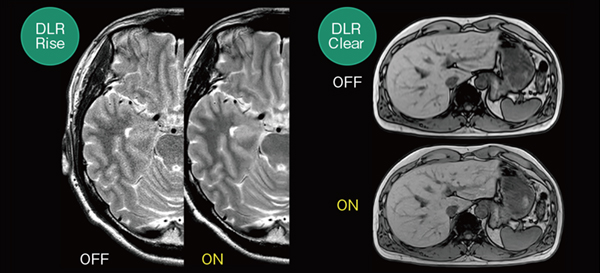

AI技術を活用して開発した「DLR Clear」は,MRIの撮像原理上発生するトランケーションアーチファクト*13の低減や画像鮮鋭度の向上が期待できます*14。また,「DLR Rise」は,AI技術を活用して開発したノイズ除去技術であり,繰り返し演算処理IP(Iterative Process)を行う高速撮像法を組み合わせることで,より短時間で高画質な画像取得が期待できます*14(図12)。これらは,すでに前バージョンで搭載されている機能ですが,今回,新たに「DLR Symmetry」が開発されました。

図12 DLR RiseとDLR Clear

DLR Rise(左)は,AI技術を活用して開発したノイズ除去技術である。DLR Clear(右)は,AI技術を活用して開発したトランケーションアーチファクト低減と画像鮮鋭度の向上が期待できる技術である。